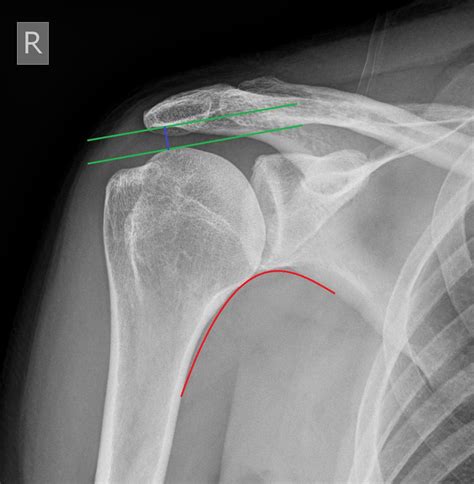

Understanding the significance of a shoulder X-ray normal result is crucial for both medical professionals and patients. A shoulder X-ray is a common diagnostic tool used to evaluate the bones, joints, and surrounding soft tissues of the shoulder. This imaging technique helps identify fractures, dislocations, arthritis, and other abnormalities. However, interpreting a shoulder X-ray normal result requires a thorough understanding of the anatomy and potential pathologies that can affect the shoulder.

A shoulder X-ray is a non-invasive imaging test that uses electromagnetic radiation to produce images of the shoulder joint and surrounding structures. This test is often the first step in diagnosing shoulder pain or injury. The X-ray can reveal fractures, dislocations, arthritis, and other bone abnormalities. However, it may not always show soft tissue injuries, such as tears in the rotator cuff or ligaments.

Interpreting a Shoulder X-Ray Normal Result

When a shoulder X-ray normal result is reported, it means that the X-ray images do not show any visible abnormalities in the bones or joints. This can be reassuring for patients experiencing shoulder pain, as it indicates that there are no obvious fractures or dislocations. However, it is important to note that a normal X-ray does not rule out all possible causes of shoulder pain.

Here are some key points to consider when interpreting a shoulder X-ray normal result:

• No Visible Fractures: The bones of the shoulder appear intact, with no signs of breaks or cracks.

• No Dislocations: The bones are properly aligned, indicating that there is no dislocation of the shoulder joint.

• No Arthritis: There are no visible signs of bone spurs, joint space narrowing, or other indicators of arthritis.

• No Soft Tissue Injuries: While a normal X-ray indicates that the bones are intact, it does not provide information about soft tissue injuries, such as tears in the rotator cuff or ligaments.